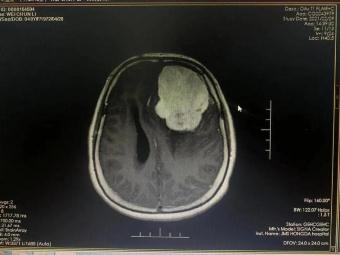

手術(shù)前 手術(shù)后

術(shù)前神經(jīng)外科與麻醉科、手術(shù)室、輸血科等科室反復(fù)認(rèn)真研究,制定了精細(xì)的手術(shù)方案和應(yīng)急預(yù)案。2月23日手術(shù)如期進(jìn)行并成功順利完成。術(shù)后第一日,患者神志清、言語(yǔ)明,對(duì)答問(wèn)題流利切題;查體配合,右側(cè)肢體肌力明顯增強(qiáng),生命指征平穩(wěn)。術(shù)后在神經(jīng)外科護(hù)理團(tuán)隊(duì)的精心護(hù)理下,患者恢復(fù)良好,可正常離床活動(dòng),目前已經(jīng)康復(fù)出院。